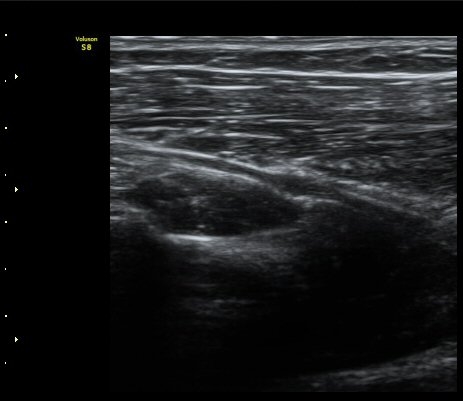

ÃÊÀ½ÆÄ °Ë»ç